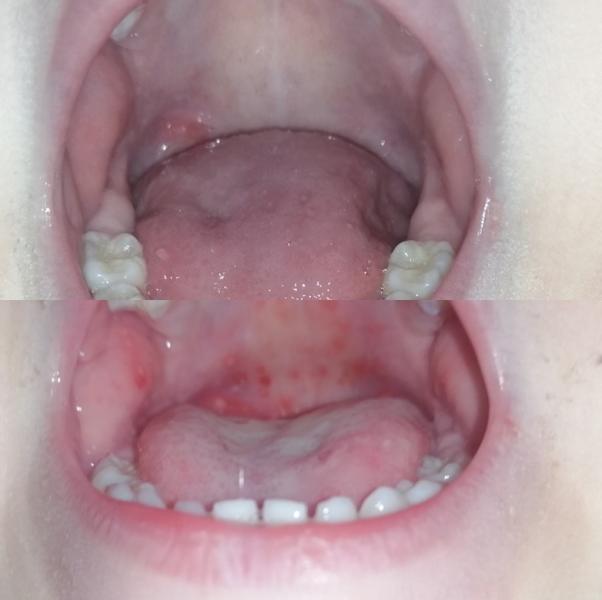

Винилин -вещь👍👍 разница в 2 дня! Значительно уменьшил стоматит

Я сама только 2 дня назад о нем узнала и очень удивлена, что такой прогресс за 2 дня! Сын ещё 2 дня назад не ел ничего, совершенно, а щас трескает все подряд, рот не беспокоит, думаю через пару дней совсем все пройдет